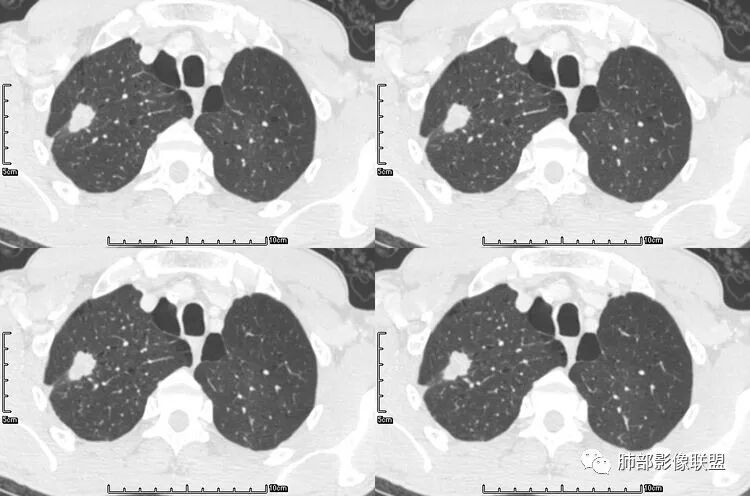

老年男性,咳嗽,咳痰带血2月,左下肺可见一团块影,深分叶,胸膜牵拉,可见坏死,坏死边界清,考虑恶性,双肺多发散在结节影,可见分叶,空洞,胸膜牵拉,考虑转移瘤;

患者老年男性,咳嗽、咳痰、痰中带血伴胸闷2月余。长期大量吸烟史。查肝肾功能、血糖、血脂、心肌酶、电解质、血沉、C反应蛋白、抗“O”、类风湿因子、抗核抗体谱无明显异常。肿瘤标志物提示NSE、CYFRA21-1稍升高。胸部CT:肺气肿背景,左肺下叶后基底段不规则肿块影,见支气管截断,内见大片状低密度区及部分血管影,增强轻度强化,远端空洞形成。双肺多发不规则实性结节影、见毛刺、胸膜牵拉及血管集束,结节内见空洞形成,部分可见血管影,多位于胸膜下。双肺见多发肺大泡。综合考虑左下肺恶性病变并双肺转移。鳞癌或淋巴瘤可能。鉴别血管炎性病变及真菌感染。

张延军:双肺多发结节,空洞影,后者洞壁厚薄不均匀,部分腔内丝丝落落,呈分叶征,边缘见毛刺影,病灶大部分位于胸膜下,与血管相连,右肺下叶前基底段结节近段支气管截断,远端见空腔。左肺下叶病灶密度不均,背段支气管壁增厚,管腔狭窄。考虑1.双肺下叶占位性病变伴肺内空洞性转移 2.多原发的占位 3.肉芽肿性血管炎代排。

本病例左肺下叶肿块,有深分叶、毛刺、胸膜牵拉凹陷、支气管截断及纵隔内淋巴结肿大等征象,都均支持病灶为恶性,如腺癌,而且叶间裂的多发结节也提示是腺癌来源可能大;双肺多发结节、肿块,大部分病灶有分叶、毛刺及胸膜凹陷的恶性征象,与原发肿瘤本身的性质有关,所以应该与左肺下叶肿块同源,而且双肺多发病灶内空洞也具有多样性;

此病例中空洞形态多样,内壁不光整,有分隔影,周围未见明显卫星灶及钙化灶,结核不太符合;患者病史慢性病史,无明显发热,缺乏中毒临床表现,急性感染基本排除;各种中性粒细胞胞浆抗体阴性,没有鼻窦炎,肾脏等病史,基本排除血管炎;霉菌性空洞常见于免疫机能低下者, 常为空洞、肺炎、伴“ 晕圈”征的结节及支气管扩张合并存在。